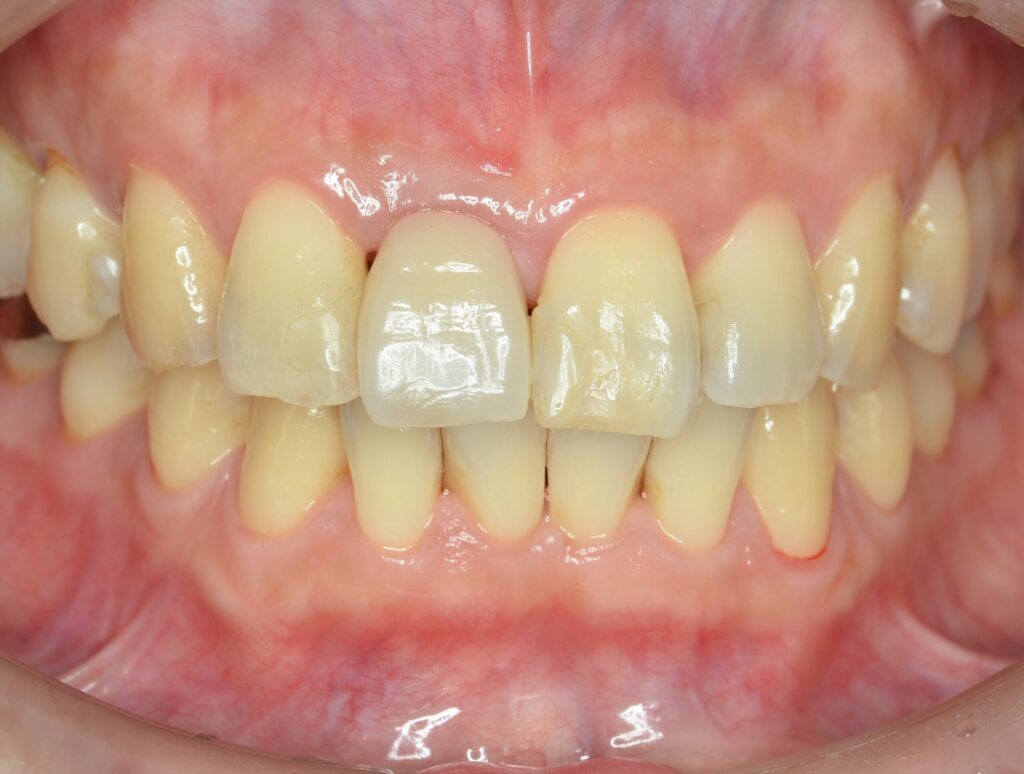

Before

After

治療内容

インプラント1本・骨造成・歯肉移植

治療期間・回数

約4ヶ月・約5回

費用

520,000円

治療のリスク

外科手術が必要になるため、患者様に体力的な負担がかかる。